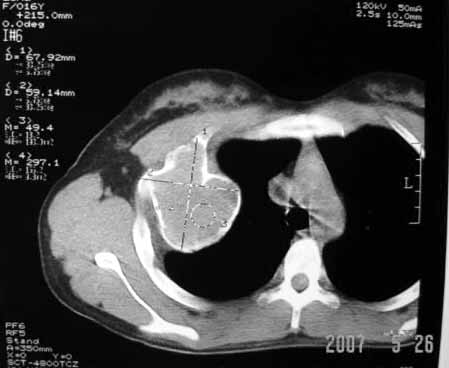

以下是引用dyqct在2007-5-26 12:01:00的发言:[br]右第二肋腋侧呈明显膨胀性、分叶状改变,内无明显间隔,ct值49hu,病变大小约67x57mm,周围硬化缘无断裂,内缘见多数骨嵴,肿块与正常骨间界限清楚。无移行带。周围软组织无浸蚀,胸膜腔无积液。[br]考虑:1、右第二肋动脉瘤样骨囊肿可能性大;[br] 2、需同骨巨细胞瘤、浆细胞瘤、骨纤鉴别。

以下是引用qiuleiyu在2007-5-26 19:50:00的发言:[br]右第二肋腋侧呈明显膨胀性、分叶状改变,内无明显间隔,ct值49hu,病变大小约67x57mm,周围硬化缘无断裂,内缘见多数骨嵴,肿块与正常骨间界限清楚。无移行带。周围软组织无浸蚀,胸膜腔无积液。[br]结合年龄考虑:1、右第二肋动脉瘤样骨囊肿可能性大;[br] 2、需同骨巨细胞瘤、骨纤鉴别。